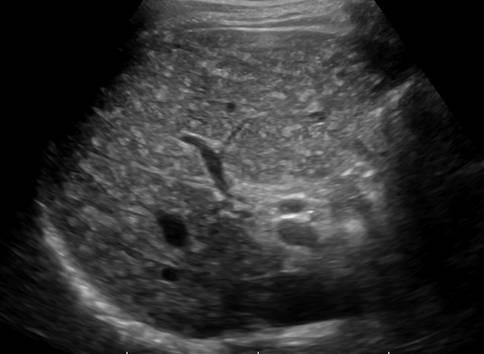

Hamartoma đường mật

» Thông tin: Nam giới – 39 tuổi.

» Lâm sàng: Kiểm tra sức khỏe.